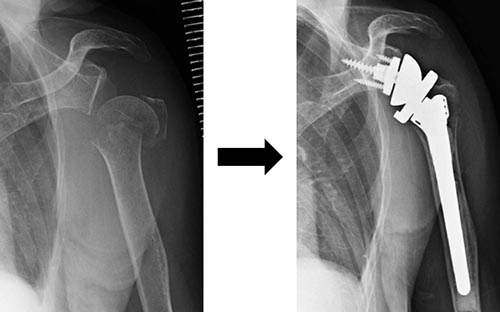

手術方法は、骨接合術は髄内釘固定法(図3)やロッキングプレート固定法(図4)が行われます。脱臼骨折の場合には、人工骨頭置換術が行われる場合もあります(図5)。近年リバース型人工肩関節置換術も用いられるようになり、臨床成績が安定しています(図6)。

図6 リバース型人工肩関節置換術